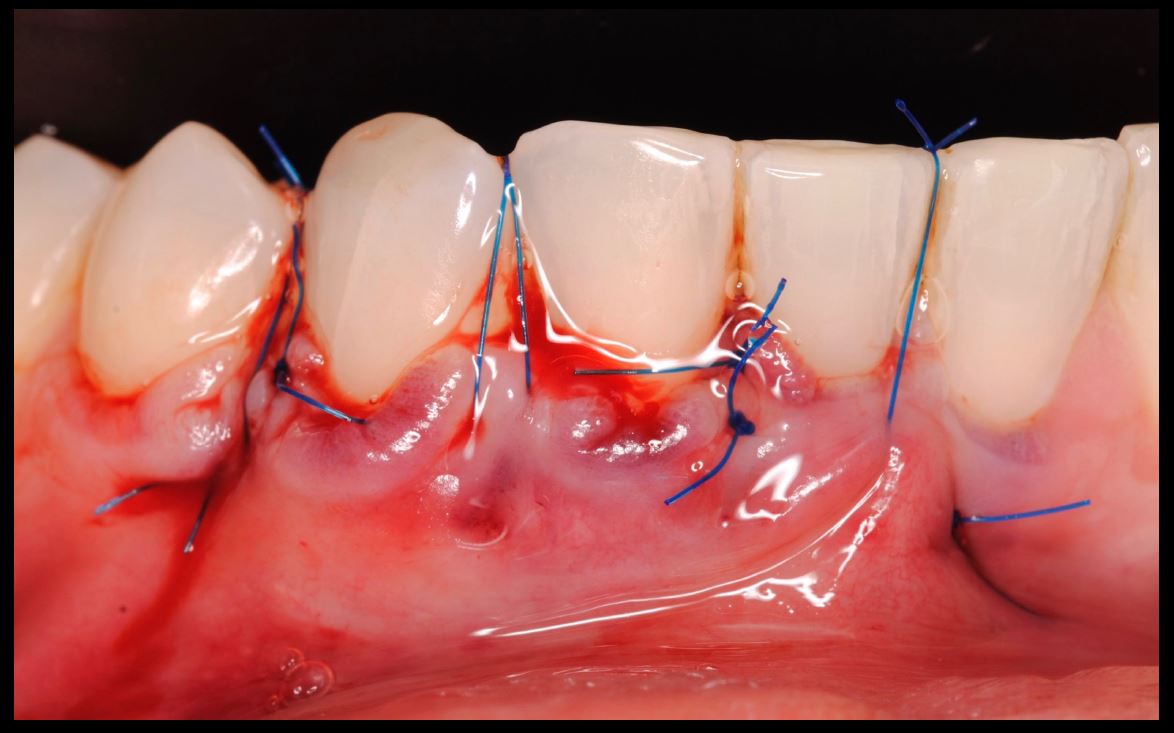

Objetivos periodontales: Mediante ingerto de tejido conectivo subepitelial de paladar con técnica de tunelización.

- Injerto de tejido conectivo libre desepitelizado de paladar + Tunelización

Fotografías del proceso: